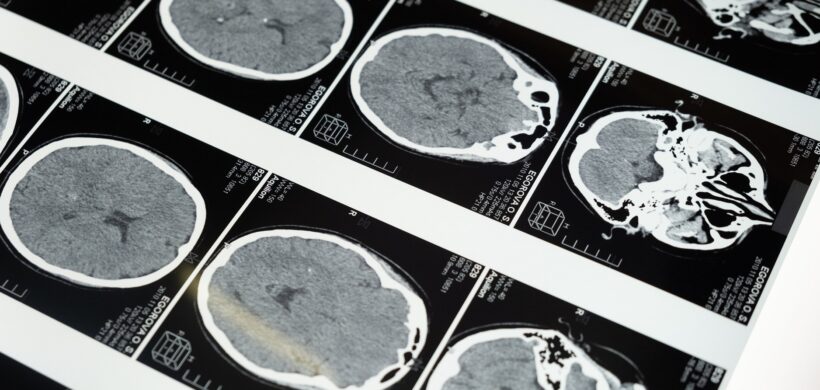

Mercedes Torrecilla | Psicóloga La demencia puede presentarse de varias maneras. La pérdida de memoria, la desorientación en el espacio y el tiempo, la dificultad para realizar las tareas diarias y las alteraciones en la personalidad y el comportamiento son síntomas comunes. En cambio, es menos conocido que las personas con demencia también pueden experimentar síntomas psicóticos. Las alucinaciones, los delirios y la agitación son algunos signos y síntomas psicóticos que pueden aparecer en la demencia. Debido a que les dificultan llevar una vida normal y limitan su capacidad de interactuar con los demás, estos síntomas pueden ser angustiantes tanto para la persona que los experimenta como para sus familiares y cuidadores. Los síntomas psicóticos no son voluntarios. Por lo tanto, el objetivo del tratamiento no es "corregir" estos síntomas, sino ayudar a la persona con demencia a sobrellevarlos de la manera más segura y cómoda posible. Para abordar estos síntomas, es primordial personalizar la atención de la persona con demencia para ofrecerle un entorno seguro y estructurado que le permita mantener la independencia y el bienestar emocional en la medida de lo posible. Se pueden utilizar las siguientes estrategias para afrontar estos síntomas psicóticos: Mantener la calma: puede ser que el cuidador se sienta sobrecargado cuando la persona con demencia presenta alucinaciones o delirios. Sin embargo, es crucial mantener la compostura y evitar mostrar signos de miedo o molestia, ya que la persona con demencia los puede percibir y angustiarse aún más. No discutir o contradecir: se deben respetar las creencias de la persona con demencia, porque si se contradicen, puede provocar irritación en ella. Es preferible desviar su atención con otra cosa o cambiar de tema. Comunicación clara: es fundamental comunicarse clara y consistentemente al interactuar con una persona con demencia. Esto puede ayudar a reducir la confusión y la ansiedad, y así disminuir la probabilidad de síntomas psicóticos. Crear un ambiente seguro y tranquilo: las alucinaciones pueden hacer que una persona con demencia se sienta incómoda o asustada. La buena iluminación y los elementos familiares, como imágenes, pueden favorecer que la persona con demencia se encuentre más tranquila. Establecer horarios y rutinas: las personas con demencia pueden beneficiarse de tener una rutina en su vida diaria. Los horarios fijos para las comidas, sueño, etc; ayudan a la persona con demencia a predecir las actividades. Estimulación cognitiva: hacer ejercicios de estimulación cognitiva puede ayudar a las personas con demencia a retrasar la aparición de los síntomas psicóticos. Los síntomas psicóticos pueden ser un aspecto difícil de la demencia. Al adaptar el cuidado de la persona y proporcionarle un entorno seguro y estructurado, es posible abordar estos síntomas y mejorar la calidad de vida de la persona con demencia.

Urrutia Amable a, S. Sosa Pérez a, D. López Brito a, A I. Peñalver Guía b, G. Bringas Sánchez b, L. Pérez Ruiz c, T. Rodríguez Obaya c, Carmen M. Valenzuela Silva c y A. Fernández Nin d | a Hospital General Docente Iván Portuondo, San Antonio de los Baños, Artemisa, Cuba. b Instituto de Neurología y Neurocirugía (INN), La Habana, Cuba. c Centro de Inmunología Molecular (CIM), Playa, La Habana, Cuba. d Centro de Neurociencias de Cuba (CNEURO), La Habana, Cuba. La enfermedad de Alzheimer (EA) es considerada actualmente la forma más común de demencia en los adultos mayores, representando alrededor del 60 al 70% de los casos. El enfoque terapéutico o farmacológico de la EA actualmente es sintomático y no curativo. Disímiles ensayos clínicos con diversos productos para el tratamiento de la EA han fracaso, otros aún continúan en la búsqueda de eficacia, seguridad o una posible cura. Desde finales del siglo pasado en nuestro país se produce la eritropoyetina humana recombinante (EPOhr), con diversos resultados científicos que han demostrado su acción hematopoyética, neuroprotectora, antioxidante, anti-inflamatoria, neurotrófica y angiogenética. Debido a ello se decidió desarrollar una eritropoyetina con bajo contenido de ácido siálico no hematopoyética (NeuroEPO); ampliamente estudiada con iguales acciones neuroprotectoras que su antecesora. El presente estudio tiene como objetivos principales evaluar la eficacia del tratamiento con NeuroEPO en pacientes cubanos con síndrome demencial tipo Alzheimer leve/moderado, en términos de la reducción en la progresión del deterioro cognitivo; así como determinar su efecto en las manifestaciones psicoconductuales. Participaron 174 pacientes con diagnóstico de síndrome demencial tipo Alzheimer leve/moderado como parte de un ensayo clínico, aleatorizados en 3 grupos con 58 pacientes cada uno: A y B recibieron dosis de 0,5 mg y 1 mg respectivamente; y C recibió placebo. Se demostró la eficacia del tratamiento con NeuroEPO, con diferencias en el puntaje del ADAScog11 al finalizar el estudio de 8 y 9 puntos en los grupos tratados con relación al grupo placebo (p=0.000, IC 95%) en la población por protocolo, mejorando también el porcentaje de cambio del CIBIC Plus (p=0.000, IC 95%), con resultados significativos en el resto de las pruebas neuropsicológicas realizadas. Además, éstos lograron una disminución de la sintomatología psicoconductual (p=0.000, IC 95%) respecto al grupo control. Como conclusiones fundamentales se evidenció una reducción en la progresión del deterioro cognitivo en los grupos que recibieron NeuroEPO con relación al grupo placebo, reflejada en la mejoría cognitiva y psicoconductual al finalizar el estudio. Acceso al artículo completo.